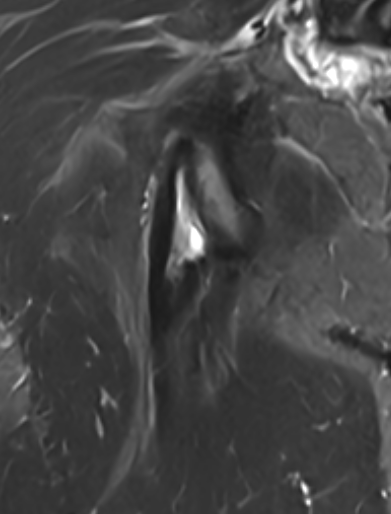

High grade partial tear proximal hamstring